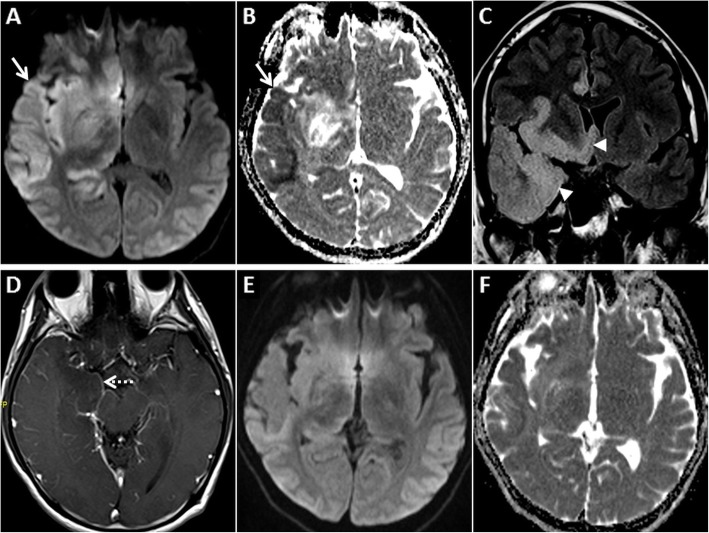

Fig. 3.

MRI of the brain in a 67-year-old female patient presenting with a seizure. GRD is observed in the right temporo-occipital region (arrow) on axial DWI (a) and ADC image (b). Also note associated cortical swelling and hyperintensity (arrow) on axial T2W image (c). Follow-up MRI after 4 days reveals complete resolution of the cortical signal abnormality and swelling on axial DWI, ADC and axial T2W images (d, e, f, respectively)

Fig 4.

MRI of the brain in a 68-year-old male patient presenting with severe hypoglycaemia. Extensive symmetric GRD (arrows) and restricted diffusion in deep white matter (arrowheads) is seen on axial DWI (a) and ADC image (b). Restricted diffusion is also seen in the putamina bilaterally (dashed arrow) on axial DWI (d) and ADC image (e). Axial FLAIR images (c, f) show hyperintense signal in the involved cortex (arrows) and in the putamina (dashed arrows)

Fig. 5.

MRI of the brain in a 46-year-old male patient diagnosed with hypoglycaemia on the background of diabetic ketoacidosis. Bilateral asymmetric GRD, more on the right, is seen in the temporo-occipital lobes (arrows) on axial DWI (a) and ADC image (b). Restricted diffusion is also seen in bilateral hippocampi (arrowheads). Mild hyperintensity is noted in the involved cortex (arrows) on the axial T2W image (c). Post-treatment follow-up MRI after 2 weeks shows partial resolution of signal changes on axial DWI and ADC images (d, e, respectively). Note that the axial T2W image also appears almost unremarkable (f)